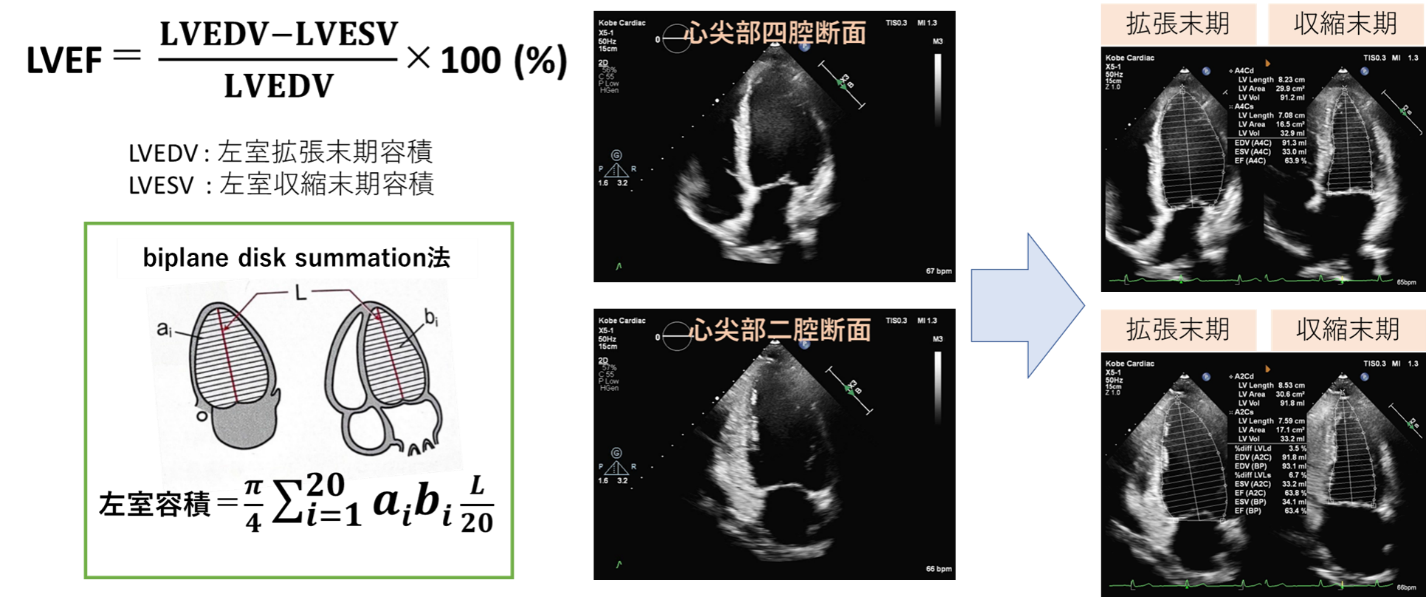

左室駆出率(left ventricular ejection fraction, LVEF)とは

左室駆出率は最も一般的な左室収縮能の指標です。心尖部四腔断面と二腔断面より,左室容積が20分割したディスクの集合体であると仮定して算出するbiplane disk summation法を用いて計測します。